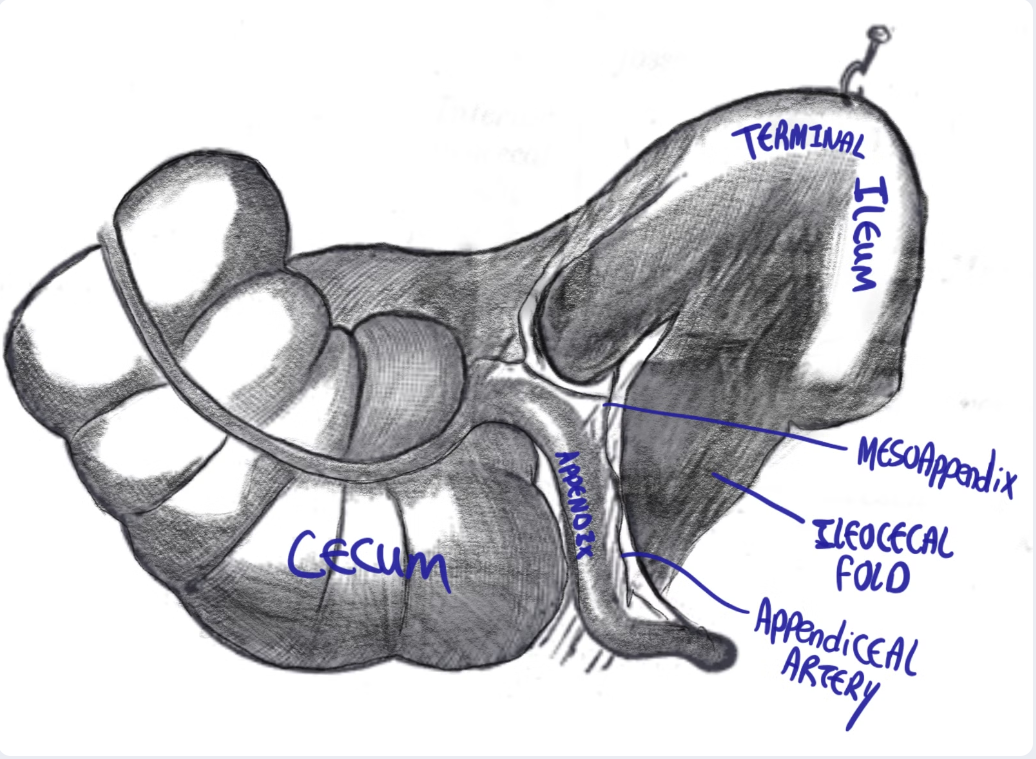

The vermiform appendix is a blind ended true diverticulum of the colon. It extends from the posteromedial aspect of the cecum, 2.5 cm inferior to the ileocecal valve, ending blindly in the right iliac fossa (RIF).

- It arises from the posteromedial aspect of the cecum.

- The appendix arises posteriorly (behind) and from the medial aspect of it.

freehand drawing showing the cecum, terminal ileum, tinea coli <!!should be “taenia coli”!!>, haustra, appendix and ileocecal fold

Appendiceal mesentery (AKA mesoappendix)

- it is a fold of peritoneum around the vermiform appendix.

- Contains the appendiceal artery and vein.

Attachments

proximal attachment:

- AKA bloodless fold of Treves.

- This is a fold of mesentery found in the angle between the antimesenteric border of the ileum and the cecum.

ileocaecal fold:

Distal attachment: extends to the tip of the appendix.

freehand drawing showing the cecum, terminal ileum, tinea coli <!!should be “taenia coli”!!>, haustra, appendix and ileocecal fold